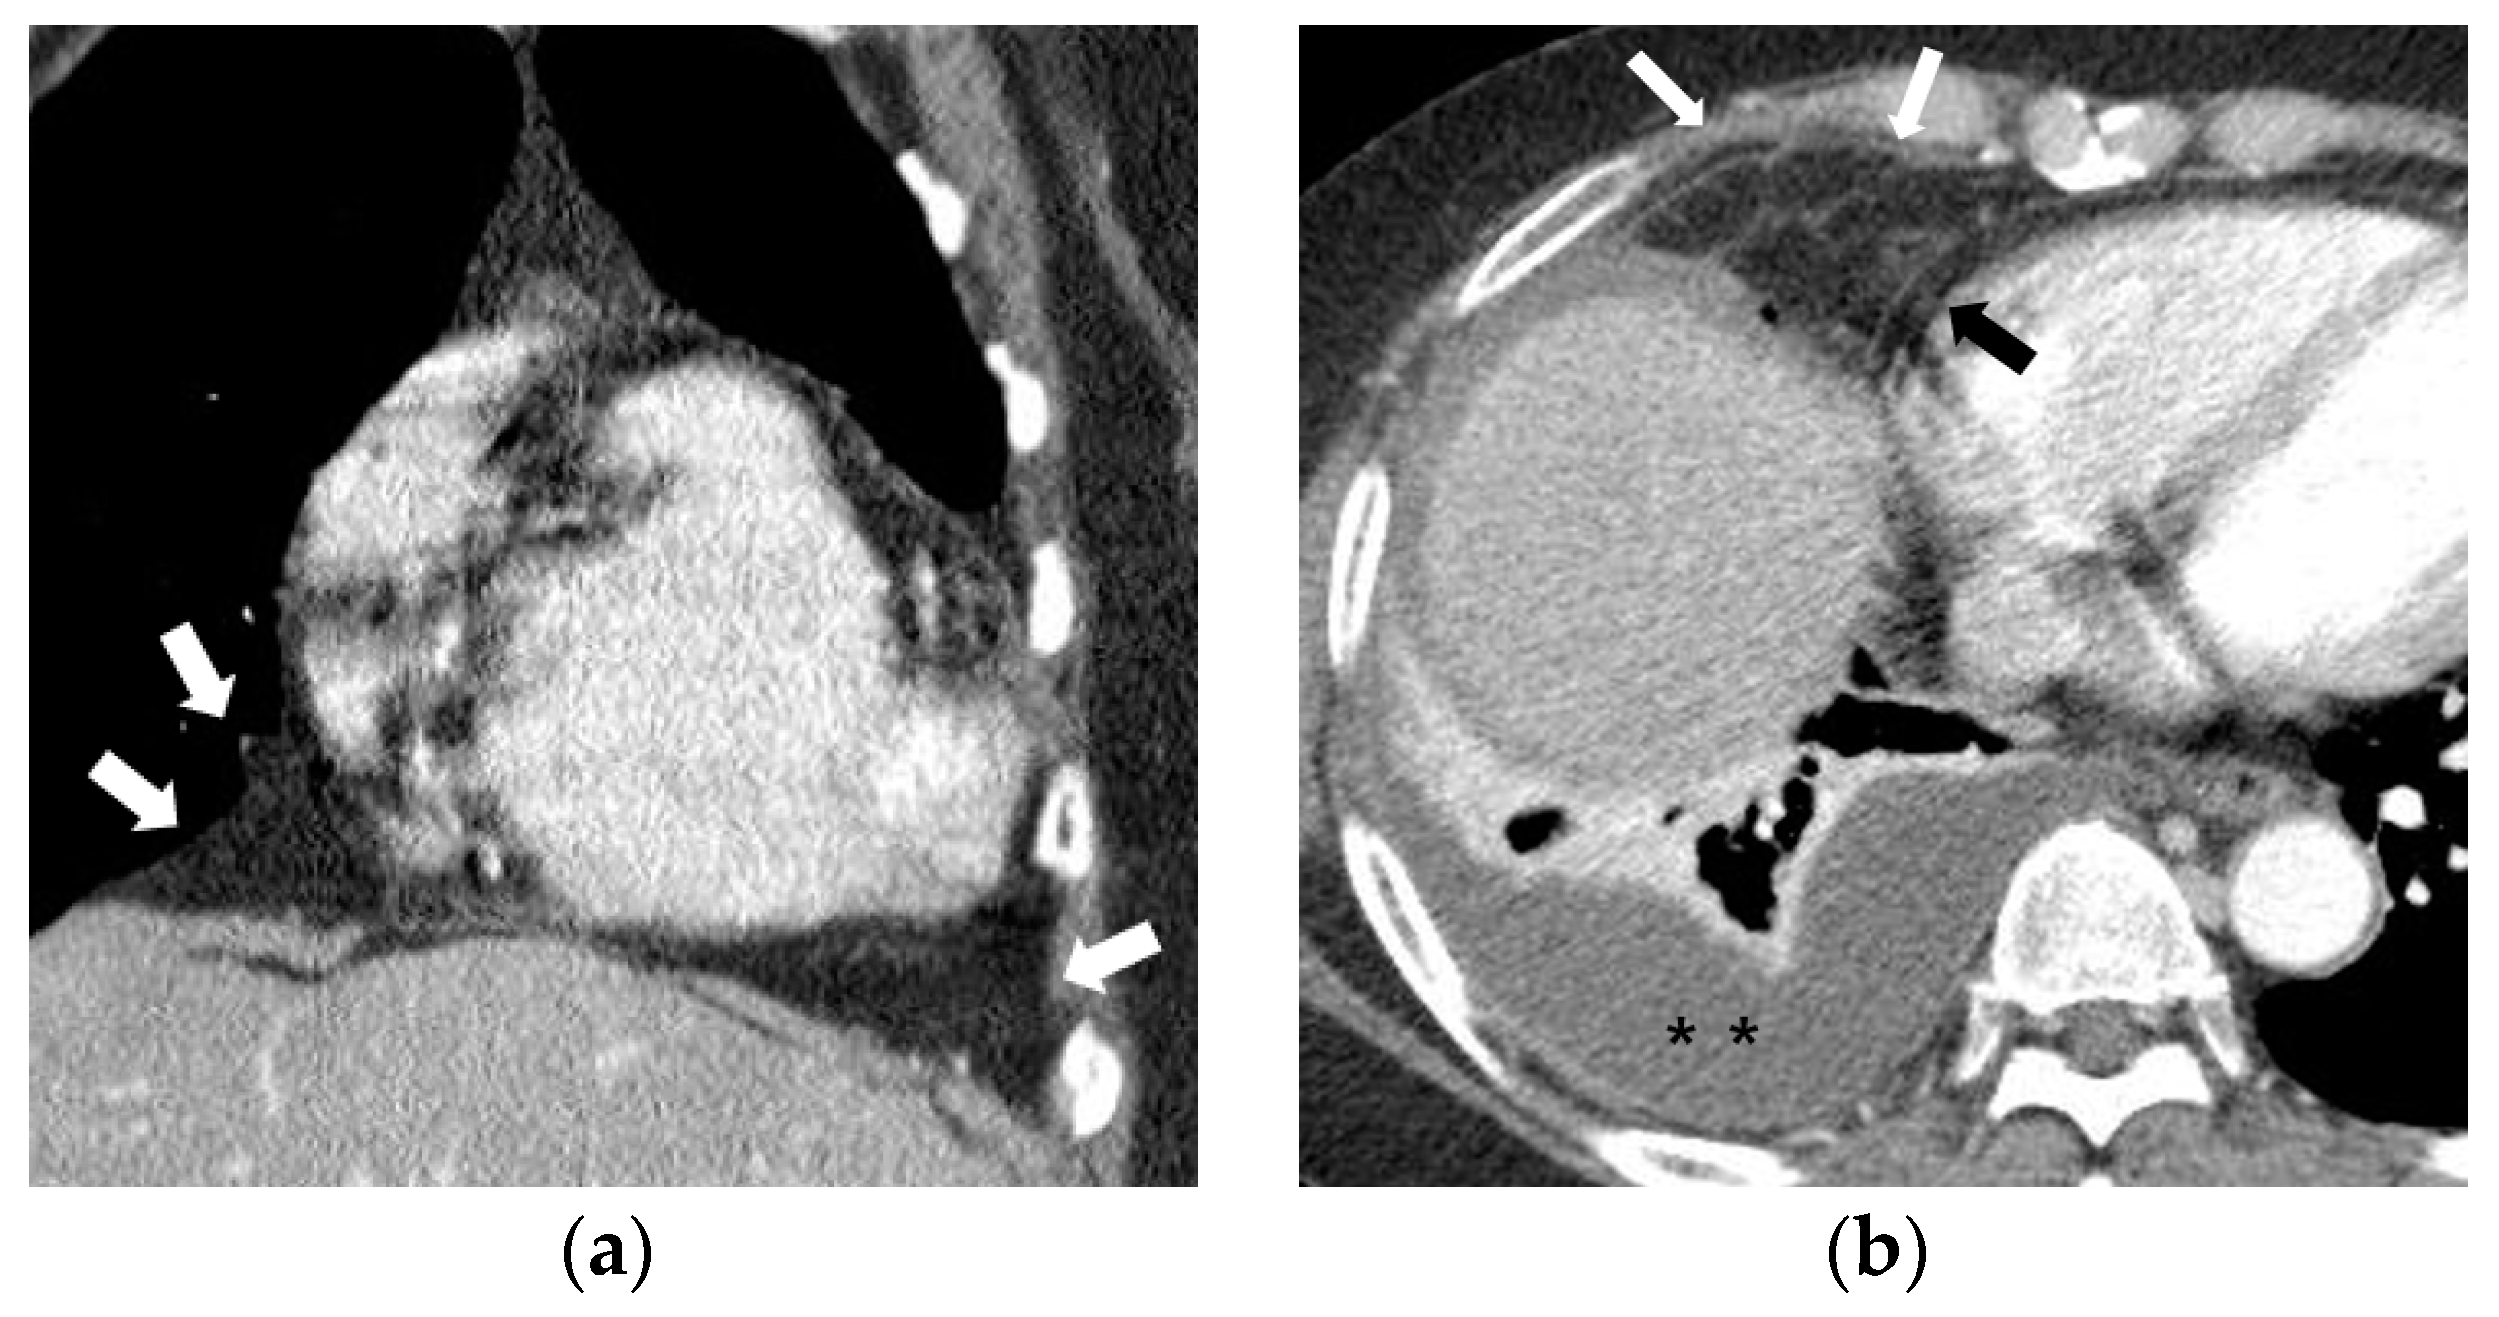

Fat attenuation with thin vessels can often be identified in the normal paracardiac area on chest CT (Figure 2a). Abnormal paracardiac fat stranding was defined as the presence of asymmetrical linear densities on the side ipsilateral to the pleural effusion, unaccompanied by tapering and branching ends, which would be more typical of normal paracardiac small vessels (Figure 2b). A paracardiac fluid collection was defined as an area of >1 cm2 with fluid attenuation (Hounsfield Unit = 0–30 on precontrast CT) (Figure 2c). An arbitrary low threshold valve of 1 cm2 was selected to avoid confusion between a subtle FC and prominent linear densities such as thick FS. Phlegmonous appearance in paracardiac fat was defined as the simultaneous presence of multifocal FS interspersed with multifocal FC in the paracardiac area (Figure 2d,e). We used the term “phlegmonous appearance” in paracardiac fat in this study due to the similarity in the CT findings of periappendiceal phlegmon in patients with appendicitis [9]. An enlarged paracardiac lymph node was considered to be present for lymph node >1 cm in short axis diameter. With respect to tuberculous immune response, we hypothesized that the extent of paracardiac fat stranding and fluid collection in the ipsilateral paracardiac fat might have a positive correlation with the strength of the immune response or inflammation within the pleural effusion. To evaluate such a relationship in pleural TB patients, we investigated whether there is a correlation between the level of pleural ADA value and serum CRP value, and the prevalence of phlegmonous appearance, or FS in the ipsilateral paracardiac fat in patients with pleural TB. Among 351 patients in pleural TB, 322 patients had available laboratory results for pleural fluid ADA level. In addition, 334 patients with pleural TB had an available blood CRP level.

Figure 2.

Representative cases demonstrating normal appearance, fat stranding, fluid collection, and phlegmonous appearance in the ipsilateral paracardiac fat on chest computed tomography. (a) Normal appearance of paracardiac fat on a coronal CT image at the level of left ventricle. Note a lack of fat stranding or a fluid collection in the paracardiac fat of a patient with pleural tuberculosis (white arrows). (b) A case of right pleural tuberculosis (asterisks) in a 67-year-old female with fat stranding (black and white arrows) in the right paracardiac fat on an axial CT image at the level of the right ventricle. (c) A case of right pleural tuberculosis (asterisk) in a 77-year-old female demonstrating a fluid collection (white arrows) in the right paracardiac fat on an axial CT image at the level of the left ventricle. (d,e) Two cases of left pleural tuberculosis (asterisk) with a phlegmon-like appearance in left paracardiac fat in a 74-year-old female on axial CT image (d), and in a 58-year-old male on coronal CT (e) at the level of the left ventricle. Note multiple fat strands (white arrows) interspersed with multiple fluid collections (black arrows or black arrowheads) in the paracardiac fat ipsilateral to the left pleural effusion.